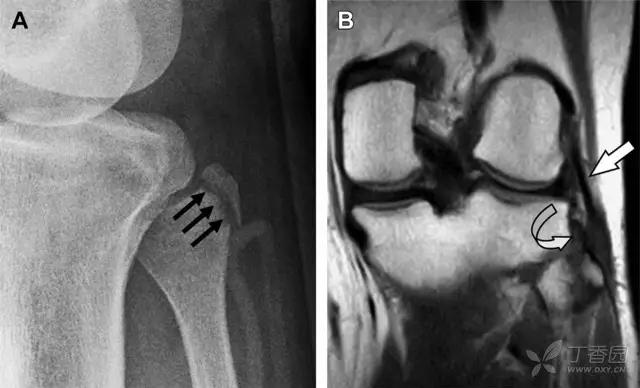

11 Segond 骨折

Segond 骨折是发生在胫骨平台外侧的垂直撕脱性骨折(图 4)。这种骨折在前后位 X 线片上显示最佳。

屈曲位时膝关节受到内旋*力暴**作用,导致皮质骨撕脱性骨折,这种骨折常发生在运动员身上。常引起股骨内髁和胫骨平台后内侧骨挫伤,75%~100% 的患者伴前交叉韧带断裂,33% 的患者伴外侧半月板损伤。

图 4 一位足球运动员的 Segond 骨折

A 正位片示关节线下方胫骨外侧皮质撕脱(箭头)。B MRI 冠状位 T1 加权像示附着于髂胫带的骨折碎片(空箭头)。